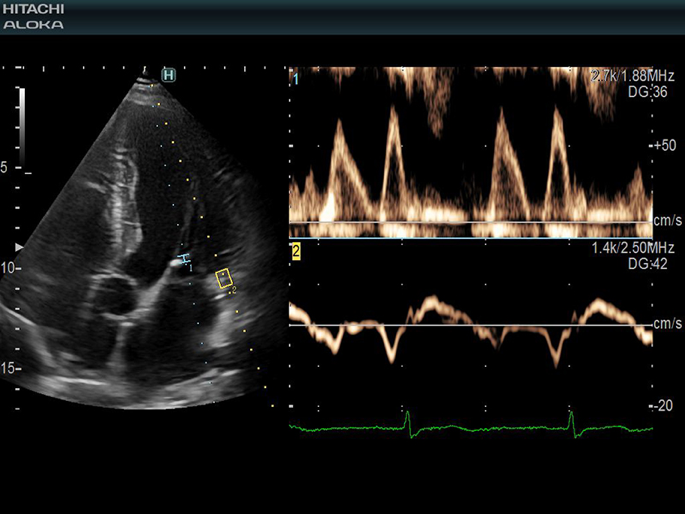

Siêu âm Doppler tim:

Xác định các bất thường của cơ tim, van tim và đánh giá chức năng vận động của tim.

Hình 5. Siêu âm Doppler tim